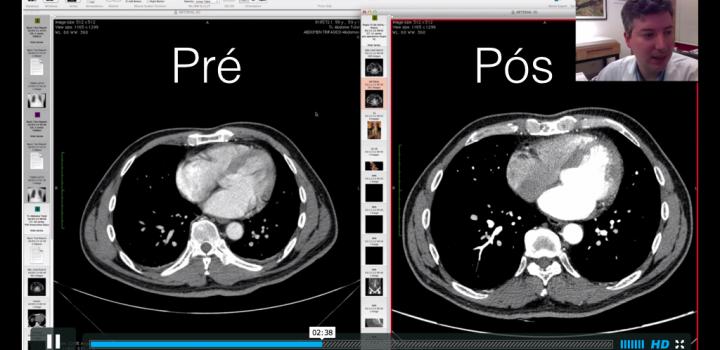

- Sincronizando exames no OsiriX